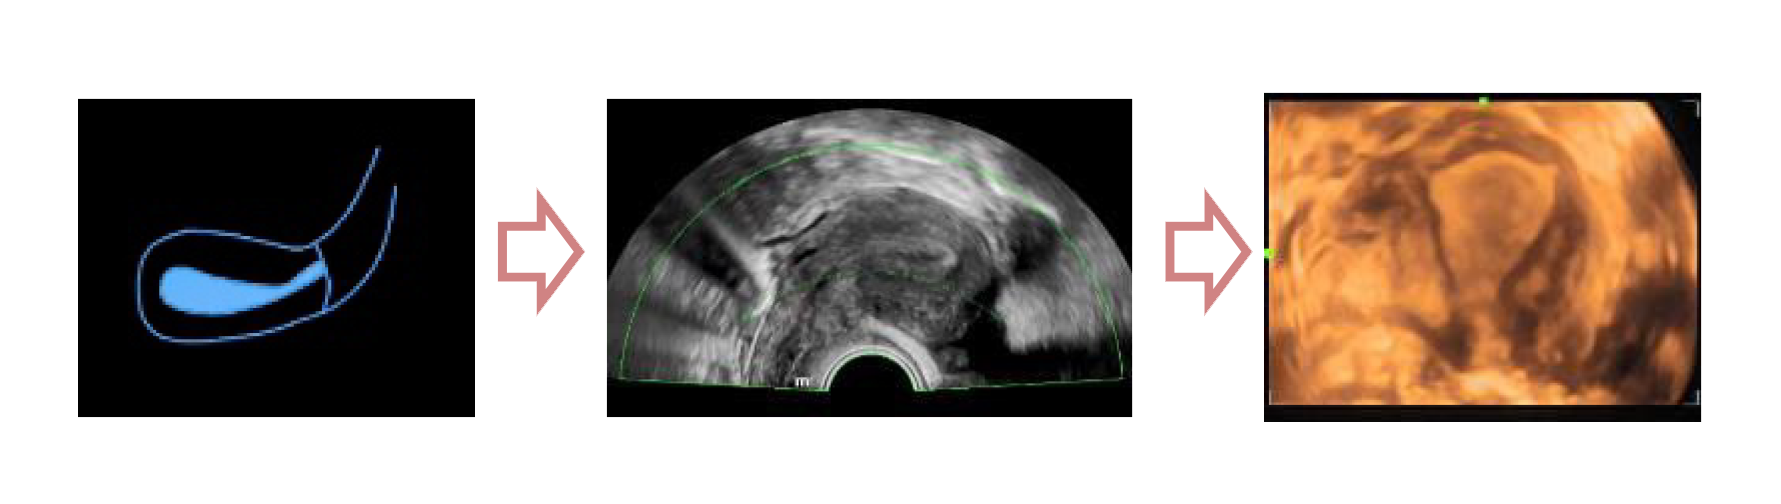

Полноценное интеллектуальное решение для диагностики матки, для легкой и быстрой оценки эндометрия

- Автоматическое распознавание матки

- Автоматическая подстройка зоны интереса и положения до оптимального

- Автоматический объемный рендеринг эндометрия